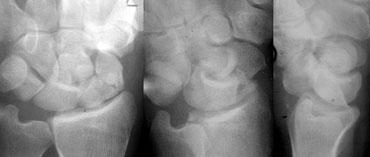

Phân tích hệ thống ca lâm sàng bên trái cho thấy những điểm sau:

1. Trên tư thế PA, tất cả các xương cổ tay đều song song với nhau, ngoại trừ xương nguyệt.

2. Cung cổ tay I và II bị gián đoạn tại khớp LT (nguyệt-tháp) và khớp SL (thuyền-nguyệt).

3. Xương nguyệt có hình tam giác.

Vì vậy, chỉ dựa vào tư thế PA, chúng ta đã có thể chẩn đoán trật khớp xương nguyệt.